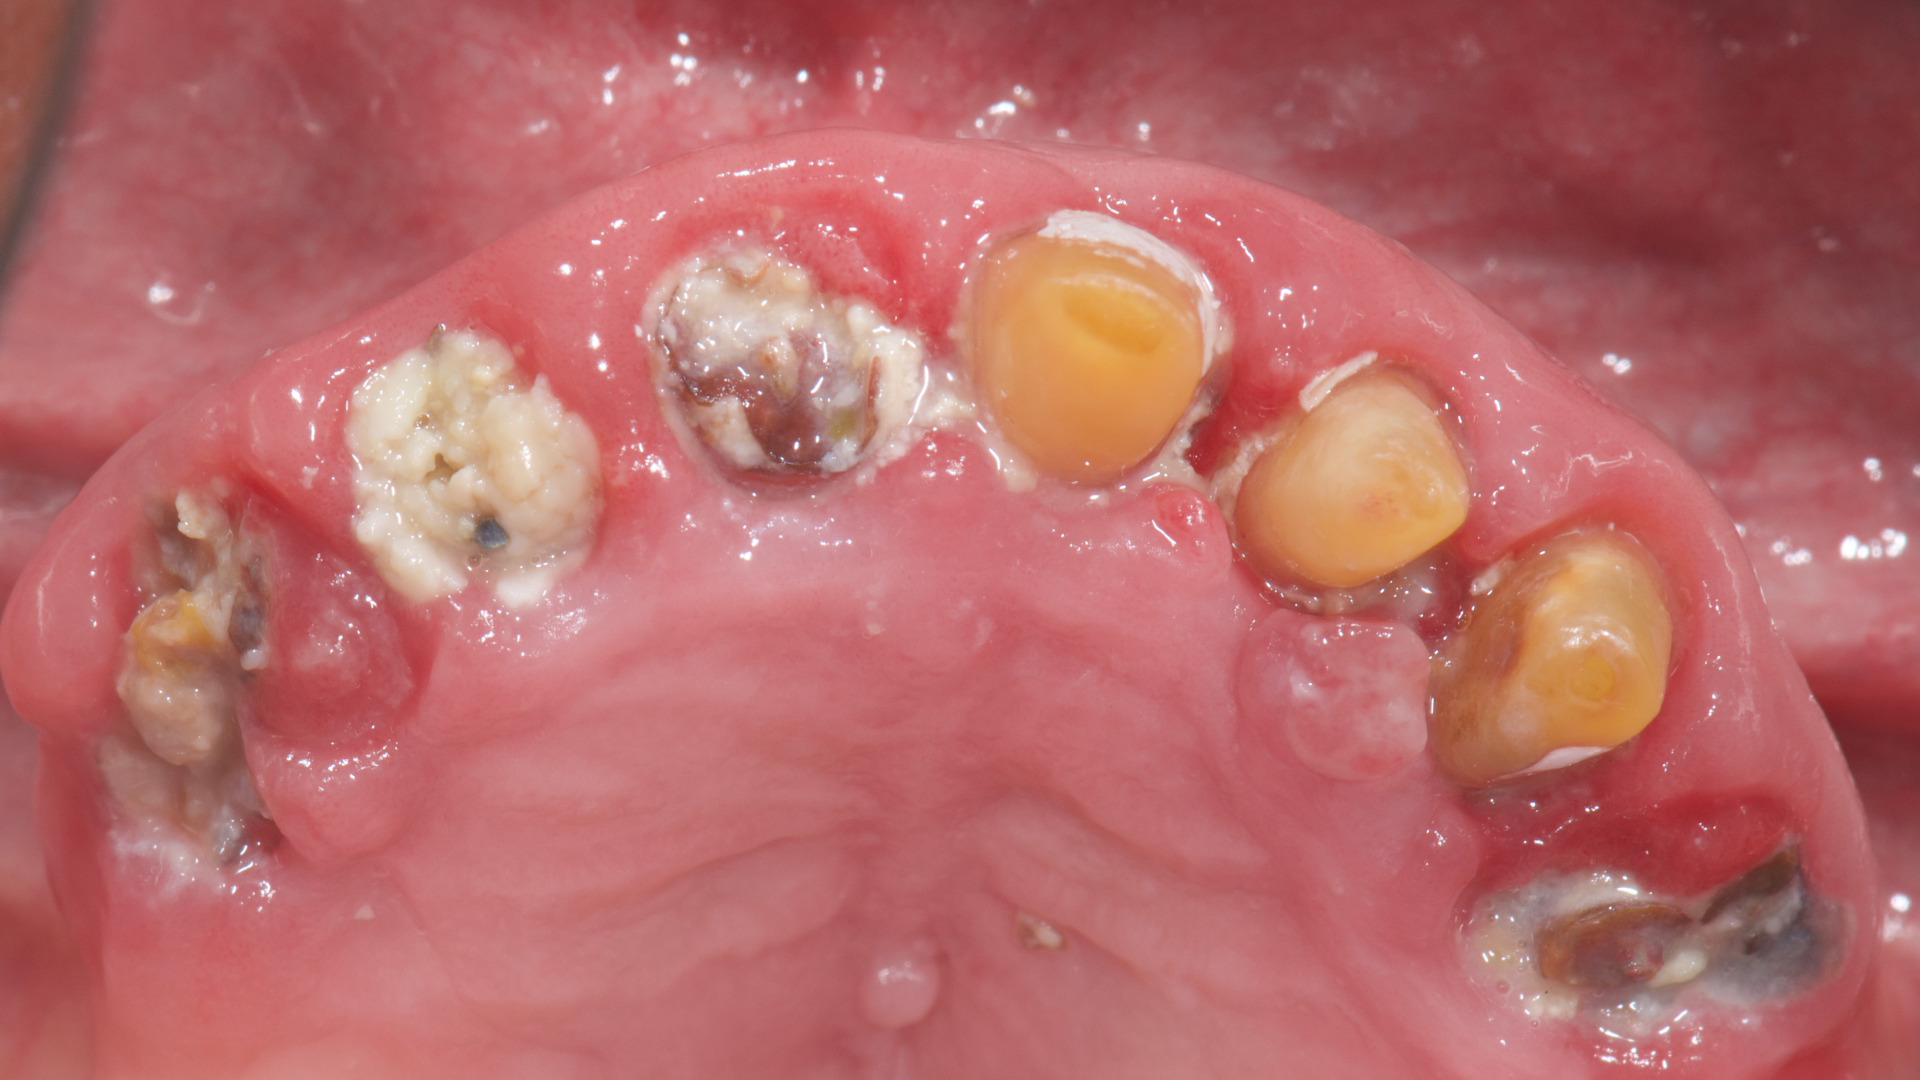

An 85-year-old partially edentulous patient was referred to our clinic for full-arch rehabilitation of the maxilla. The patient was in good general health and a non-smoker. His primary complaints included difficulty in chewing, maxillary pain and occasional halitosis. Clinical and radiographic evaluation revealed a short-span fixed metal–ceramic prosthesis supported by seven anterior maxillary teeth. The prosthesis had debonded, and four of the abutment teeth were structurally compromised. The remaining three showed varying degrees of caries and periodontal problems. A diagnosis of failing dentition was established (Figs. 1 & 2).

At the initial visit, digital impressions were captured using the Medit i700 scanner to document the residual teeth, soft tissue, existing prosthesis and opposing arch. The occlusal records were obtained at the current vertical dimension of occlusion and in centric relation. Mandibular movements were recorded with the zebris JMA jaw registration system (zebris Medical). Intra- and extra-oral photographs were also taken. A virtual diagnostic wax-up and a digital smile simulation were created based on these records (Smile Creator, exocad). Finally, eight implants were planned (Figs. 3 & 4) according to the new wax-up (exoplan 3.1, exocad), and both a surgical guide and a metal-reinforced temporary prosthesis were fabricated in advance (Figs. 5–7).